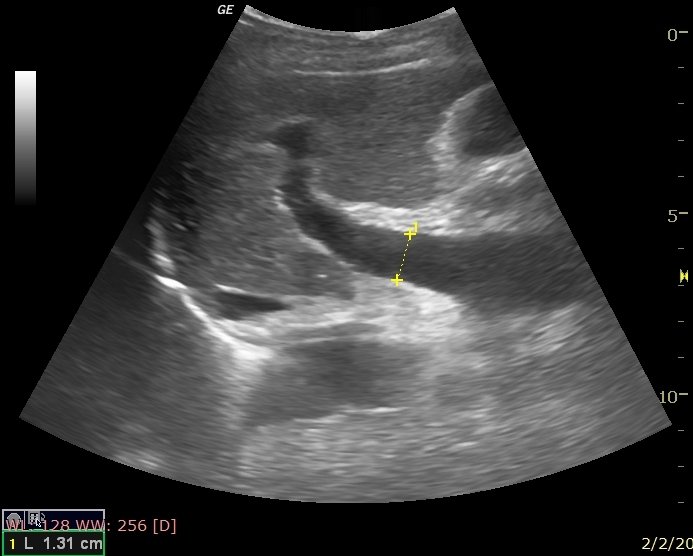

La ecografía hepato-portal es un estudio de diagnóstico por imágenes que utiliza ultrasonido convencional y Doppler para evaluar el hígado y el sistema venoso portal, responsable de transportar la sangre desde el aparato digestivo hacia el hígado.

Permite analizar tanto la estructura hepática como el flujo sanguíneo en la vena porta y sus ramas, siendo fundamental en pacientes con enfermedades hepáticas crónicas.

- Vena porta

- Ramas portal derecha e izquierda

- Venas hepáticas

Se evalúa tamaño, textura hepática y dirección/velocidad del flujo sanguíneo.